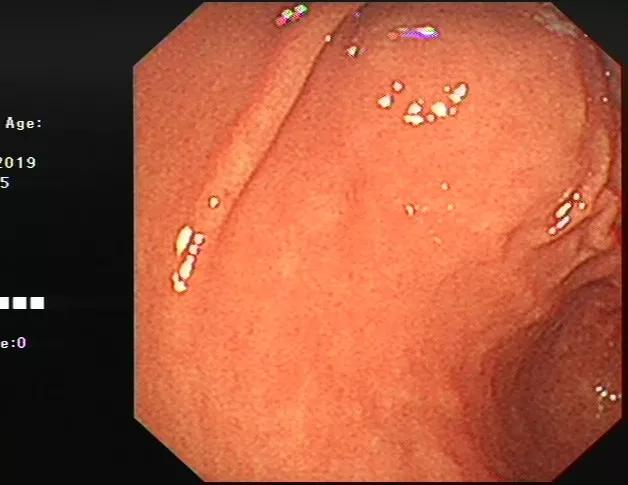

比如我们发现了十二指肠一个粘膜下隆起(下图),但是无法判断他的性质。

通过超声内镜,我们可以看出它在哪一层,是什么结构、什么性质。见下图: